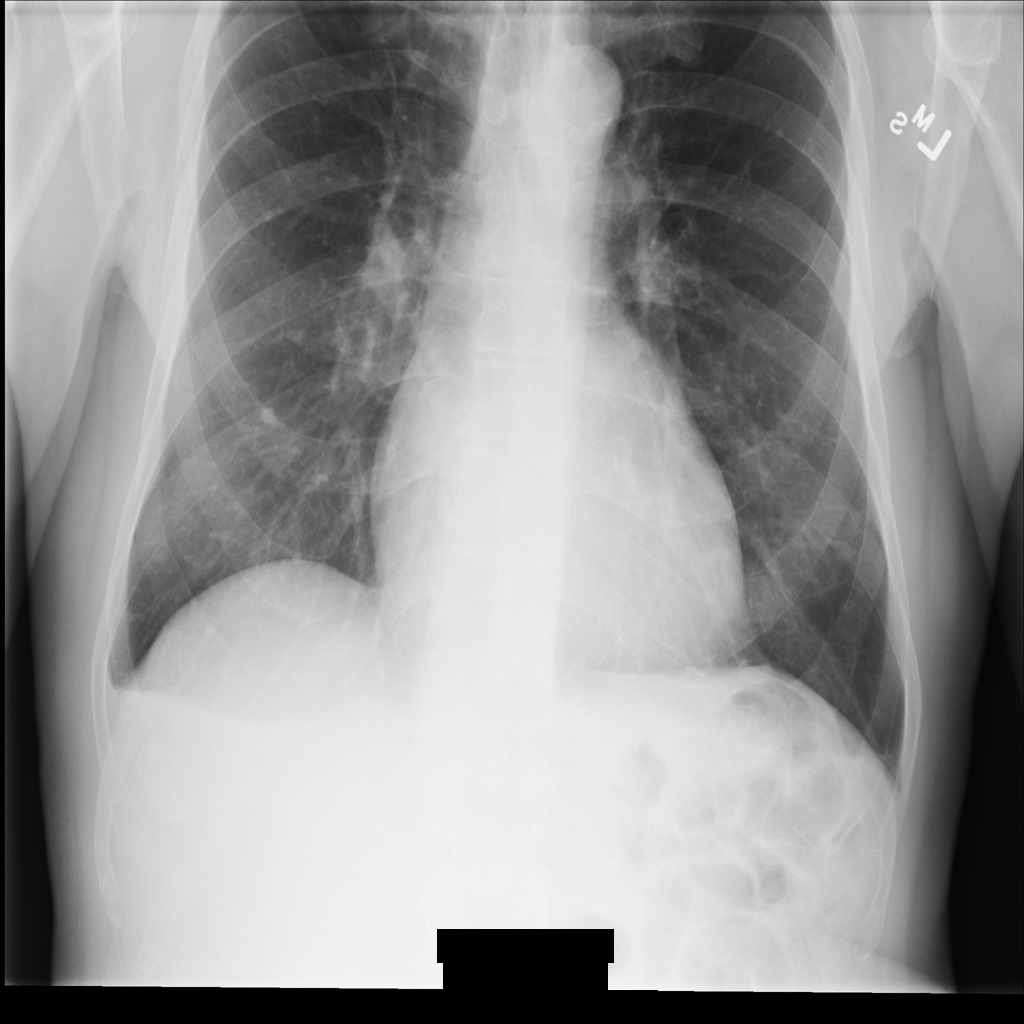

As secções seguintes mostram o aspeto da imagem na instância DICOM e os metadados na instância.

Imagem de exemplo

Alguns exemplos nesta página contêm uma saída da imagem desidentificada. Cada exemplo usa a seguinte imagem original como entrada. Pode comparar a imagem de saída de cada operação de desidentificação com esta imagem original para ver os efeitos da operação: